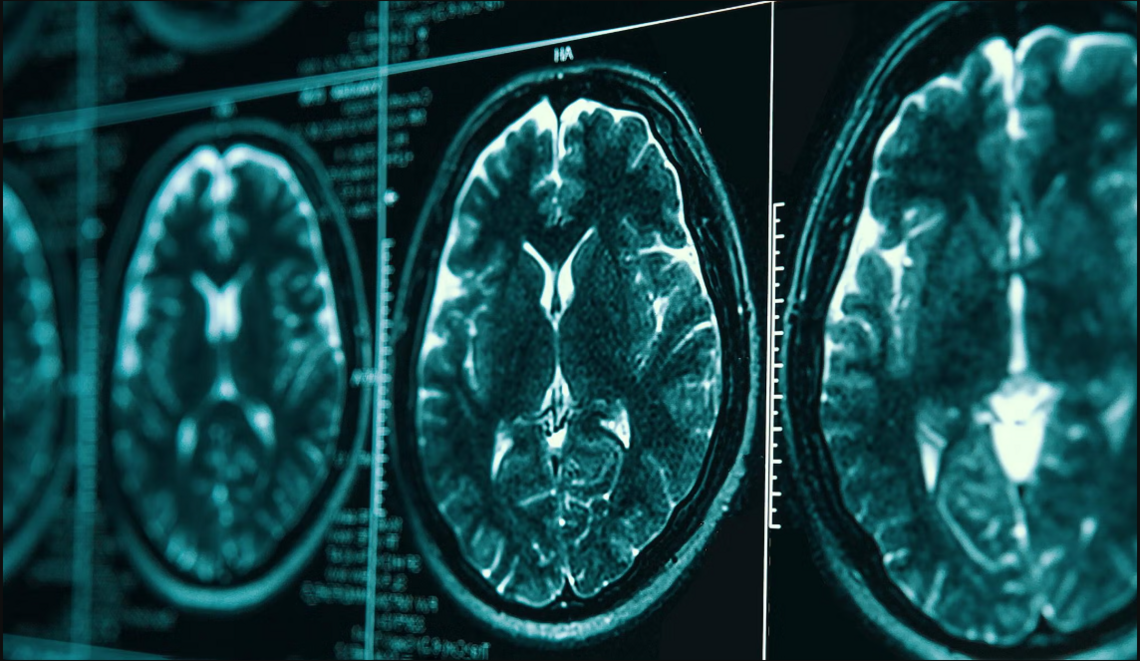

The Predementia Neuroimaging of Transient Ischemic Attack (PREVENT) study investigates the connection between transient ischemic attacks (TIA) and the development of late-life dementia over a five-year period. Magnetic resonance imaging (MRI), cognitive tests, and blood biomarkers are used to measure biosignals that occur before cognitive decline. This study aims to diagnose dementia at an earlier onset, to give TIA patients better outcomes in the future.

The Stroke Immune Mediated Pathways and Cognitive Trajectory (Stroke-IMPACT) study aims to understand post-stroke cognitive decline by focusing on a possible maladaptive immune response.

Simple Perfusion Reconstruction Algorithm (SPIRAL) is a clinical study that tests a new imaging algorithm designed to better detect acute stroke more effectively and efficiently at a lower cost. By improving this algorithm, we hope to improve future outcomes for patients that have suffered acute stroke.